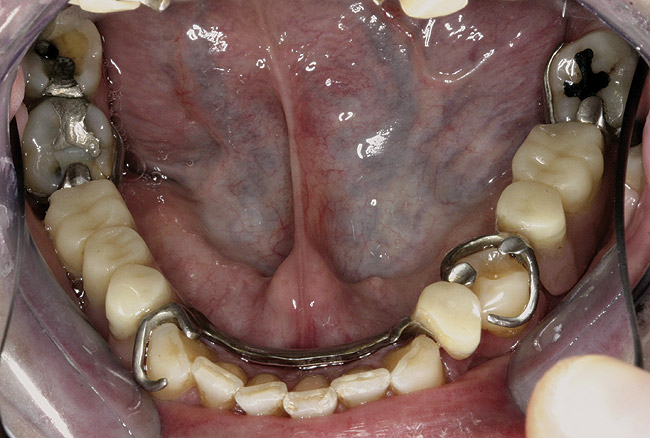

Figure 3  Intraoral occlusal view of mandibular dentition with the existing removable prosthesis presenting excessive signs of wear.

Figure 3

Initial examination revealed a partial edentulous patient with extensive wear of the maxillary anterior teeth and moderate wear in the mandibular teeth (Figure 1, Figure 2, Figure 3 , Figure 4, Figure 5, Figure 6 and Figure 7). The patient's maxillary and mandibular RPDs also showed excessive wear and multiple signs of fractures (Figure 2 and Figure 3). The patient had been wearing a mandibular nightguard for 8 years.